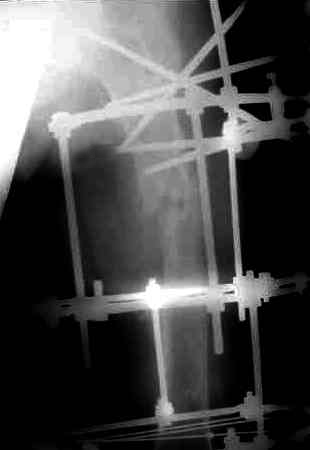

После нескольких некрэктомий, проведения аутодермопластики и заживдения ожоговой раны через 2 месяца после травмы произведен открытый остеосинтез левой бедренной кости штифтом и пластиной (деротационной) [image 01, 02]. Через 1 год и 7 месяцев после травмы у больного диагностированы ложный сустав и хронический остеомиелит левой бедренной кости. Произведено удаление металлических фиксаторов, секвестрэктомия и остеосинтез бедренной костивнешним двухплоскостным стержневым аппаратом [image 03, 04] .